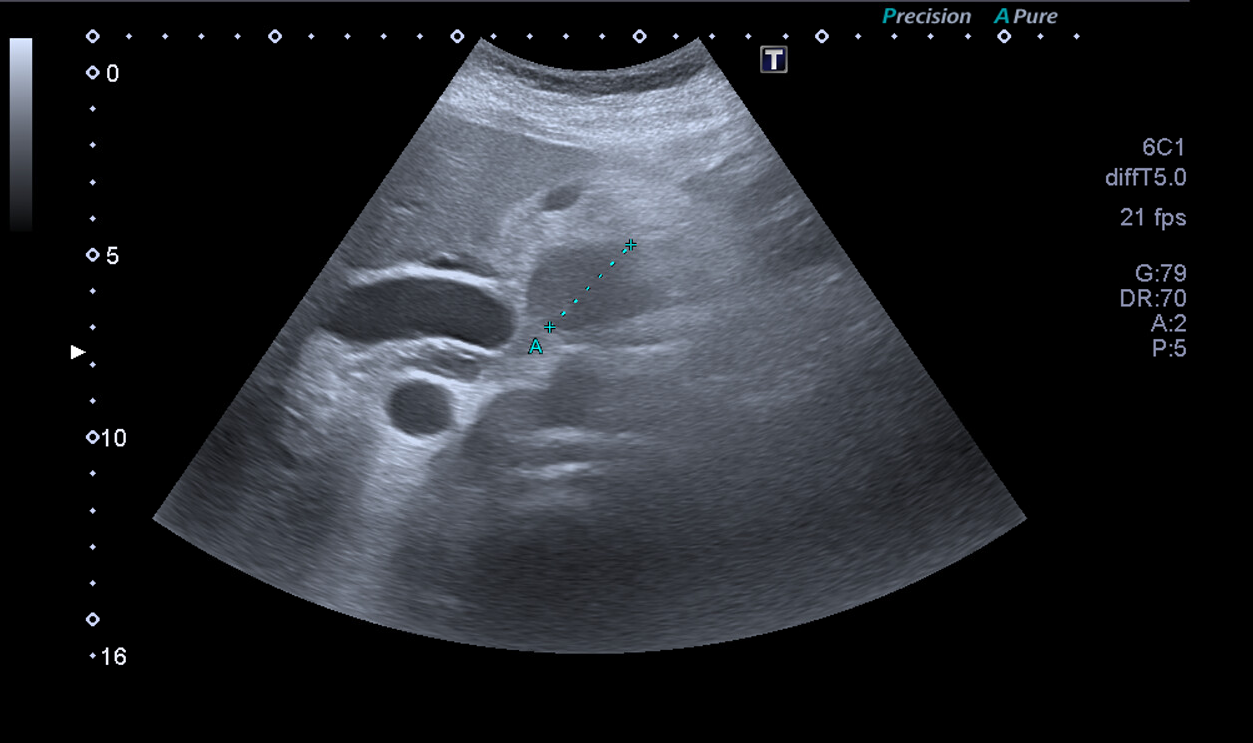

Ante la situación de dolor abdominal hacemos ecografía a pie de cama: se evidencia imagen redondeada de contenido heterogéneo de aproximadamente 38 mm, con dos imágenes redondas anecoicas en su interior en cabeza de páncreas. Restos de la exploración ecográfica sin alteraciones.

Juicio Clínico: Imagen redondeada de contenido heterogéneo de aproximadamente 38 mm.

TC Abdominal: Neoplasia de cabeza de páncreas con manguito de tejido neoplásico que engloba totalmente la AMS, y trombosis completa del confluente espleno-porto-mesentérico.